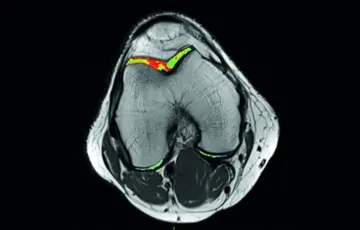

OLEASPORTMEDIZIN

UNSERE HERSTELLERNEUTRALE MRT-LÖSUNG FÜR DIE SPORTMEDIZIN LIEFERT WICHTIGE INFORMATIONEN ZU MUSKEL-, KNOCHEN- UND GELENKERKRANKUNGEN SOWIE EINE KLARERE SICHT AUF DIE BEURTEILUNG VON LÄSIONEN UND DIE FRÜHERKENNUNG VON GELENKVERÄNDERUNGEN.